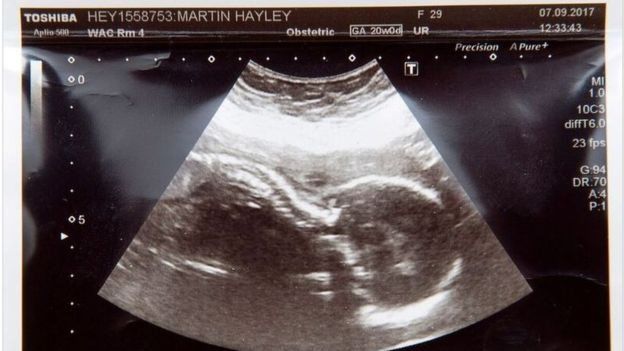

Женщина узнала, что малышка рискует умереть при родах на 20 неделе беременности, потому как у ее ребенка редкое врожденное заболевание - двусторонняя агенезия почек.

По словам матери, она довольно рано почувствовала, что с ее беременностью происходит что-то не то. Фото: Trainglenews